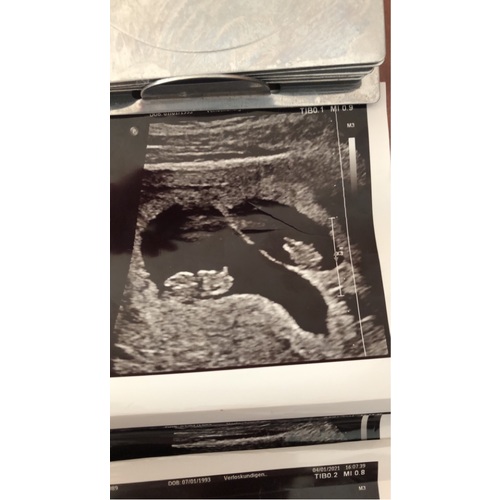

Wij zijn voor de eerste keer in verwachting 鈾ワ笍 na jarenlang proberen en vruchtbaarheidsbehandelingen kregen wij 2 weken geleden het nieuws in verwachting te zijn van een eeneiige tweeling. Zo niet verwacht maar zo welkom 馃グ

Wij hebben vandaag een echo gehad met 10+3 weken. En toch een verrassing: het is een eeneiige tweeling. Ze waren gelukkig even groot en lekker beweegelijk. Vanaf nu elke twee weken een echo.

Update vandaag precies 10.0 wkn zwanger en 2 hele mooie hartjes mogen horen. 馃グ